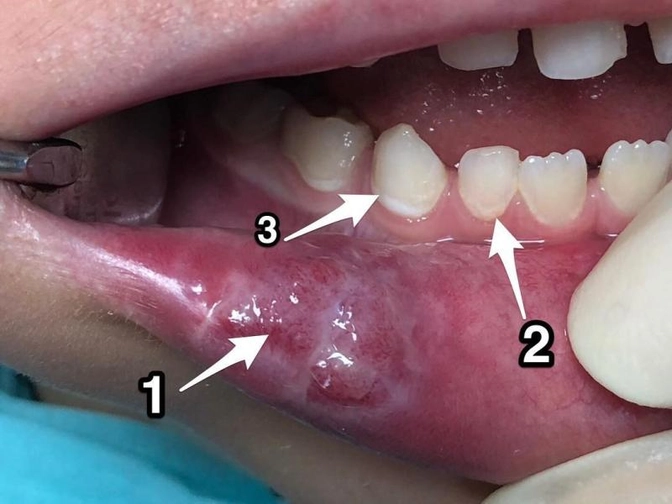

Травма губы.

А когда «отмерзло», то обнаружилось вот такое ( 1 )

Это - самое распространённое осложнение после анестезии.

Иногда нажёвывают до жутчайших отеков.

2 - смотрите сколько налёта вдоль десны

Стараемся чистить лучше

Иначе будет кариес

Вот так он выгладит - на фото обозначен 3.